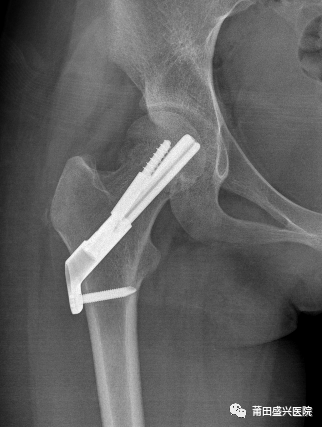

經(jīng)盛興醫(yī)院骨科團(tuán)隊(duì)綜合評(píng)估后,決定為患者實(shí)施“右股骨頸骨折微創(chuàng)復(fù)位FNS內(nèi)固定術(shù)”治療。在林國(guó)兵院長(zhǎng)、黃益平主任醫(yī)師及骨科團(tuán)隊(duì)的共同努力下,手術(shù)于2022年1月18日在麻醉科及手術(shù)室醫(yī)護(hù)的全力配合下順利完成,術(shù)后透視復(fù)位佳,內(nèi)固定位置良好?;颊咝g(shù)后1周康復(fù)出院。

(術(shù)后1個(gè)月復(fù)查)